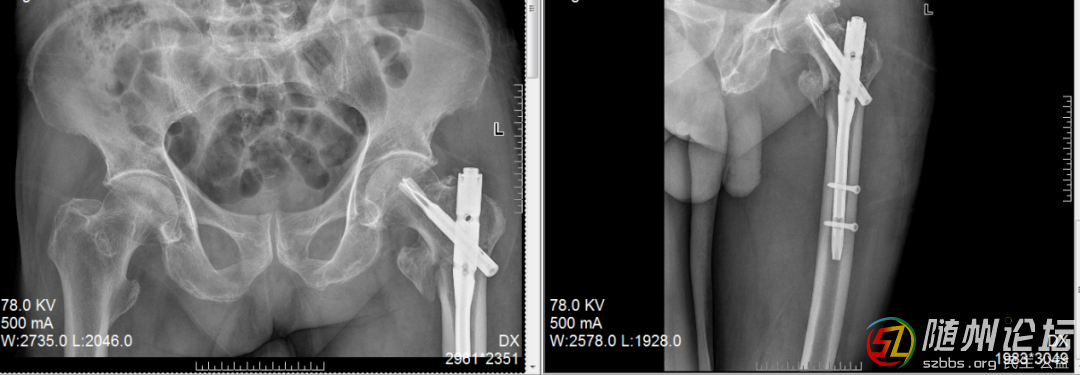

高齡老人髖部骨折,降低臥床風(fēng)險(xiǎn)

一位高齡老人摔傷導(dǎo)致髖部骨折,我們采用了微創(chuàng)的“鑰匙孔”式微創(chuàng)內(nèi)固定術(shù)。手術(shù)時(shí)間短、出血少,老人第二天就可以在床上坐起、活動(dòng)腿腳,一周內(nèi)嘗試站立,大大降低了長(zhǎng)期臥床的風(fēng)險(xiǎn)。